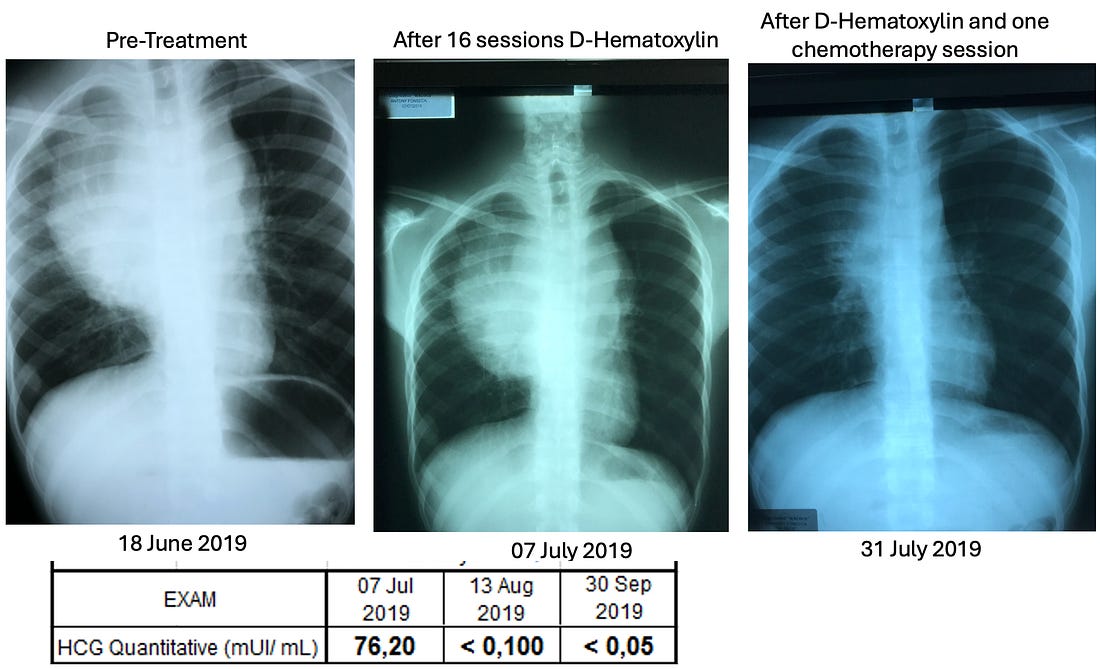

advice). •He felt very strongly about the necessity of chelation therapy in cancer (e.g., to prevent subsequent heart attacks following successful D-hematoxylin treatments—which occurred years later in some of Tucker’s cases) and to that you should not give leukemia patients with anemia iron as the cancer needed that to grow (to the point he would sometimes also chelate iron in leukemic patients). •McCann was also very focused on cultivating bacteria on a target media that would dissolve specific biological targets (e.g., he cultured bacteria from a dead cow’s cataract and then found it could eliminate other cataracts; likewise, he found this approach worked for cancer). Note: my experience with individuals like McCann is that some of their insights are spot on while others they have a deep conviction in are ultimately not correct. The Next PhaseLike many alternative therapies, D-hematoxylin grew up in “the Wild West” of alternative medicine. This was made possible by its very low toxicity profile, which allowed it to be used in humans at widely varying doses without significant side effects. Fortunately, the threads keeping D-hematoxylin from being lost eventually converged in Ecuador with a doctor who’d successfully treated 44 out of 45 cases of microbiologically confirmed chronic bacterial prostatitis using DMSO combined with antibiotics that were applied directly into the bladder (much in the same DMSO is FDA approved to treat interstitial cystitis) who then tested negative for any infection 15-20 days following treatment (with no subsequent recurrences), demonstrating DMSO's ability to counteract bacterial resistance. Note: interestingly, Stanley Jacob, was still alive when these treatments were initiated (he died in 2019 at age 91). At the start of the prostatitis treatments, the doctor in Ecuador contacted him for advice, and Jacob encouraged the experiment, agreeing it was a good idea, even though he hadn't heard of anyone attempting it before. As he’d heard of McCann through Ecuador’s medical community, these prostatitis successes inspired that doctor to try intravesical DMSO mixed with hematoxylin for a prostate cancer patient (which was administered in the same manner and frequency as his prostatitis treatments). This worked, and he gradually began using it for other prostate cancer patients and then other cancers as well, which gradually grew into a fifteen-year research project on the therapy (which he's shared with me over the course of a few months). Note: I also know of one individual who used D-hematoxylin intrarectally over a prolonged period to locally treat a cancer there, but the data on this approach is still limited. Recent D-Hematoxylin PatientsThat

project involved treating approximately 85 patients, with the cure rate

in patients who had not previously received chemotherapy averaging

between 80-90%. As such D-hematoxylin is an excellent cancer treatment

but it is not perfect and will not work for everyone. •Leukemias (particularly acute leukemia) Note: myeloproliferative neoplasms (e.g., polycythemia vera, essential thrombocythemia and primary myelofibrosis) depend upon a mutant protein for survival which was shown to be susceptible to disruption by a few small compounds including hematoxylin. While D-hematoxylin has not been tested on these disorders, this study (along with the other known effects of DMSO and D-hematoxylin) suggest it could be an effective treatment for them. The cancers with a poorer response included: •“Solid” tumors Additionally, if there is a cancer marker associated with the tumor (e.g., CEA or PSA), it will often rapidly drop, making it very easy to track the progress of D-hematoxylin. As the following cases show, many of the improvements were quite profound: •A 54-year-old female patient with Classic Hodgkin Lymphoma which had invaded 72% of her bone marrow, with CD20-positive expression. She had a variety of symptoms (e.g., recurrent pleural effusions and anemia), but since her religion did not permit blood transfusions, she received only D-hematoxylin and EDTA and then had a full recovery (with no recurrence in twelve years of follow up). The most striking aspect of this case was the change in her bone marrow biopsy, after three months of treatment with D-hematoxylin (unlike chemotherapy) it selectively destroyed the cancerous cells, allowing normal ones to regrow and rapidly addressed her anemia. •A 72 year old patient with leukemia who was anemic and had her anemia rapidly improve following D-hematoxylin: Likewise, similar bone marrow changes were seen in her. Note: another similar leukemic patient on D-hematoxylin with anemia had no improvement. After investigating, it was determined this was due to her regularly using WD40 on a daily basis (without respiratory protection) and hence having a bone marrow intoxication which was directly damaging the bone marrow (and in turn the leukemia diagnosis may have been incorrect). •A 16 year old male with a mediastinal seminoma that received 16 D-hematoxylin infusions, 5 IV vitamin C infusions and then one chemotherapy session (on July 7) where cisplatin and bleomycin were combined with DMSO (after which he continued chemotherapy and has recovered from the cancer). •A 63-year-old male with cholangiocarcinoma (a rare, aggressive and notoriously difficult to treat cancer of the bile duct) who received D-hematoxylin plus chelation and vitamin C (but no chemotherapy). During his successful treatment, a drain from his bile duct was also monitored for tumor markers. Additionally, the cancer debris could be seen in the drainage tube (an internal-external percutaneous transhepatic biliary drainage catheter)—something which the Ecuador doctors now view as essential to have if D-hematoxylin will be used in this cancer: Note: another bile duct cancer patient (a 68 year old female) received palliative D-hematoxylin while waiting for surgery and chemotherapy (which ultimately could not be done because of how advanced the cancer was). Her cancer markers levels significantly improved following D-hematoxylin (and continued to reduce during gaps in treatment), but she eventually lost the will to live and passed after 16 months. •A 63-year-old man with B-cell lymphoproliferative disorder who received D-hematoxylin for 10 days (with no other treatment), experienced a significant drop (normalization) of his white blood cell count during that time then stopped at the advice of his hematologists, and two years later died from COVID. •A man who had a stable bladder polyp which became cancerous following a covid vaccination (with the initial sign being a large blood clot in the urine) which when examined had spread in a large portion of the urinary tract’s endothelium. It was surgically removed, but due to how far it had spread, the urologist told the patient he would only survive for two months. They then began five weeks of intravesical and IV D-hematoxylin, and in four years, the cancer never returned (which led to the urologist telling everyone about the “amazing” surgical procedure they had performed). •A 55-year-old female who had a mediastinal tumor (type unknown as it was wrapped 560° around the aorta and hence could not be biopsied) which fully resolved after 33 daily D-hematoxylin treatments. Additionally, this was the CT prior to treatment where the tumor can be seen around the aorta: While this was the CT two weeks following the D-hematoxylin treatment: Lastly, at five years follow up, there was no recurrence. •A 27-year-old female with acute lymphoblastic leukemia reacted poorly to two sessions of chemo, was classified as terminal, and then was started on D-hematoxylin. She had a significant improvement in her cancer and simultaneous improvement in her anemia which continued long after conventional treatments for anemia were halted (which did not include blood transfusions as she was a Jehovah’s Witness). In a before (1-2-2020) and after (2-1-2020) video I saw of this patient, she initially looked very frail and had difficulty walking, while just a month later (after 31 days of treatment), she had no difficulty walking and looked vibrant and robust. Additionally, they continued to monitor her on a monthly basis, and four years later, she’d had a healthy baby, and had her hematocrit range from 42 to 48 (which is slightly above average) indicating she had no further risk of anemia (even though hematologists in the hospital had predicted her reckless pregnancy would cause severe anemia). Additionally, her ESR (which had been significantly elevated prior to treatment) normalized (and remains normal 5 years later). Lessons from EcuadorIn addition to observing a remarkable degree of success from D-hematoxylin, the Ecuadorian team was able to discern a variety of patterns (many of which mirrored Tucker’s previous observations) that helped craft their treatment protocols. For example: •While DMSO alone can somewhat help with cancer, the effects of DMSO combined with hematoxylin are completely different from what would be observed with DMSO alone. •They saw many signs during their treatment protocols that D-hematoxylin selectively targeted cancer cells. •Cancers did not develop resistance to D-hematoxylin (which is a common challenge with many chemotherapies). •While some tumors rapidly disappear, other types frequently become avascular (which stops their growth) and dried-out, blanched, or fibrous rather than being directly shrunk (e.g., I reviewed cases where a brain cancer simply stopped growing). In many cases, those tumors are then very easy to extract surgically. Note: to my knowledge, everyone besides that Ecuadorian team who treats with D-hematoxylin still uses Tucker’s protocol and has not tried to improve upon it. Variations in D-Hematoxylin EfficacyOn